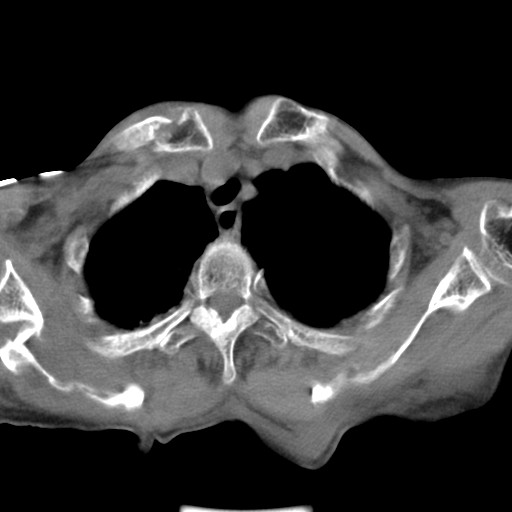

标题: CT21467:女,93岁,摔伤后检查。

女,93岁,摔伤后检查。

右肩甲骨粉碎性骨折,上传骨窗

右侧锁骨\\肩胛骨骨折、右侧湿肺,心功能不全伴双侧胸腔积液,右下肺膨胀不全,左膈破裂或食管裂孔疝,冠脉钙化,心包少量积液,请上传骨窗.

右肺炎症,心功能不全伴双侧胸腔积液,右下肺膨胀不全,食管裂孔疝,冠脉钙化,心包少量积液,左侧肋骨骨折,右肩甲骨粉碎性骨折。93岁,高寿哇!

右肺炎症,心功能不全伴双侧胸腔积液,右下肺膨胀不全,食管裂孔疝,冠脉钙化,心包少量积液,左侧肋骨骨折,右肩甲骨粉碎性骨折。